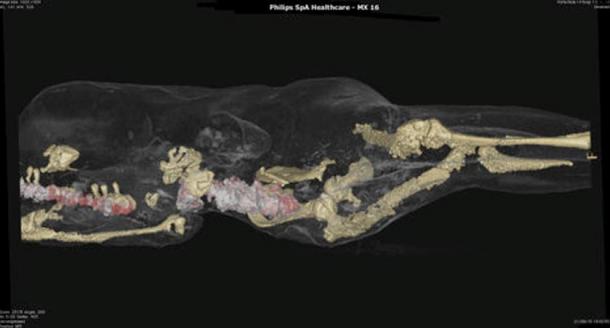

Il existe aussi des moulages d'animaux comme des cochons et des chiens; tous ont parfaitement été préservés au moment de leur mort, lorsque la nuée ardente submergea la ville après l'éruption du Mont Vésuve en 79 après JC, enterrant la ville pendant 1800 ans.